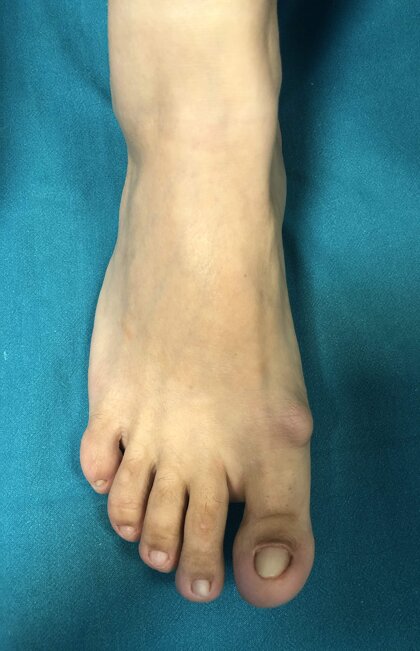

In alto a sinistra foto pre-operatoria piede destro in pz con Alluce Valgo.

In alto a destra ed in basso a sinistra radiografie pre-operatorie dei piedi sotto carico in AP e LL. La pz è stata operata con accesso mini-invasivo, per l’osteotomia del I MT non sono stati utilizzati mezzi di sintesi metallici ma un pin riassorbibile; nel caso specifico non ho effettuato l’osteotomia di F1 I dito in quanto la qualità dell’osso non era ottimale